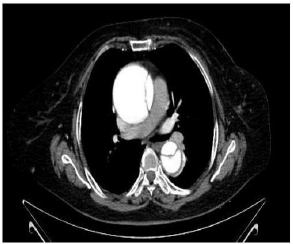

Homem de 57 anos, com antecedente de hipertensão arterial sistêmica, em uso de Clortalidona 25 mg, enalapril 20 mg 12/12 h e anlodipino 10 mg 1x dia, procurou o prontosocorro com queixa de dor torácica, “em rasgando”, de grande intensidade irradiando para dorso. O eletrocardiograma não apresentou alterações significativas. Realizou o exame reproduzido abaixo.

Sobre o caso, o diagnóstico e a conduta são, respectivamente,